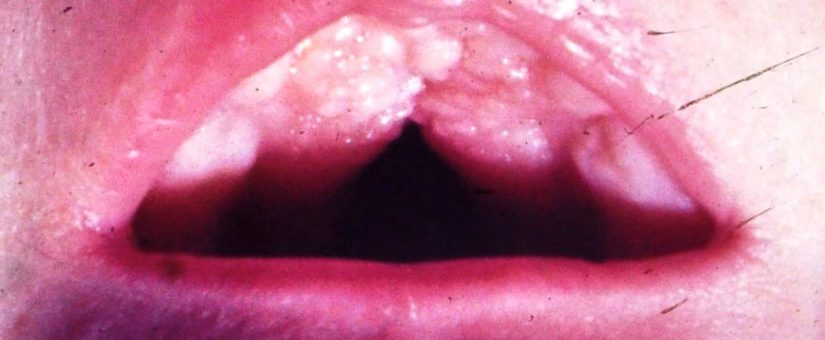

I (W. Wertelecki, M.D.) see two illustrations of palatal tori, in essence, an overgrowth of the palatal bone along its midline – often it represents the lack of modulations by the opposing tongue – noted in instances of hypotonia, microglossia, micrognathia, etc. NOTE that it is easy to mistake deep gaps separating palatal tori for a cleft of the hard palate.

Please see standard medical information sources regarding “high arched” hard palates, pseudo-clefts, tori, etc.